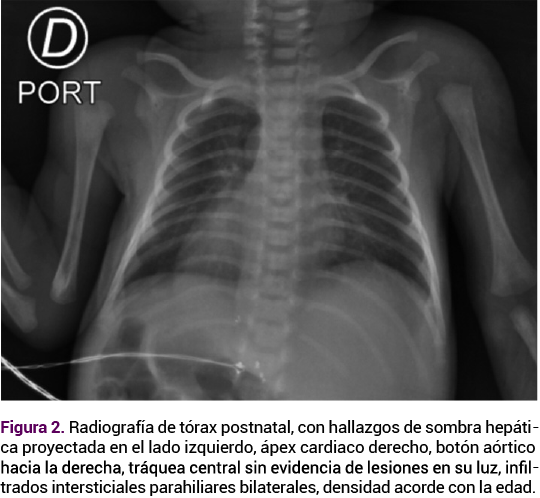

Los estudios postnatales del neonato con diagnóstico prenatal de situs inversus incluyeron una ecografía transfontanelar normal, así como una radiografía de tórax (Figura 2) y ecografía de abdomen, que confirmaron los hallazgos descritos, sin otras alteraciones, también se obtuvo el cariotipo neonatal que descartó alteraciones numéricas o estructurales en los cromosomas.

<strong>Figura 2</strong>

Figura 2.